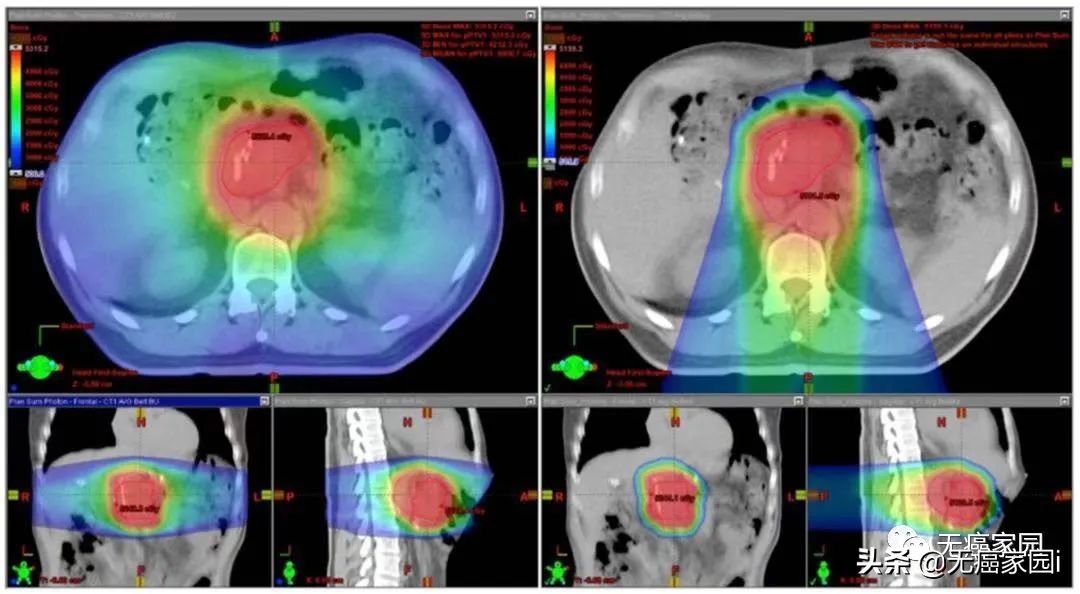

多项剂量学研究证实,与IMRT相比,质子治疗可减少无法手术切除或切除术后胰腺癌患者正常组织的照射剂量。

宾夕法尼亚大学的研究人员发现,对于无法手术切除的胰腺肿瘤患者,双散射和笔形束质子治疗可降低胃、十二指肠和小肠的照射剂量,同时只轻微增加了十二指肠和胃的中至高剂量区。研究人员还分析了切除术后的胰腺肿瘤患者,质子治疗计划相较于X线放疗可显著减少左侧肾脏、胃和脊柱的临床相关剂量;与X线放疗和双散射质子治疗相比,笔形束扫描质子治疗可减少右侧肾脏、肝脏和小肠的照射剂量。

质子治疗(右)与X线放疗(左)治疗胰腺癌的剂量学比较